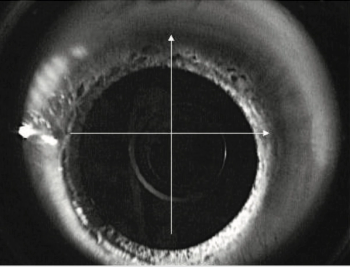

Advancements in imaging make ICL an effective option for a wider range of patients.